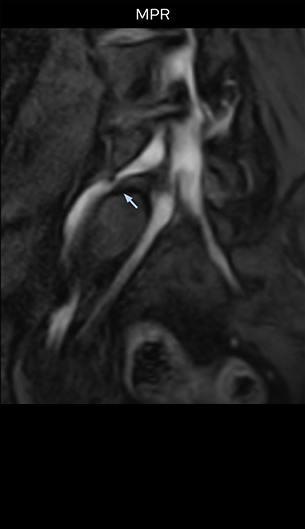

“The intra-luminal signal of veins, especially around the intervertebral space, can be suppressed well with NerveVIEW. As a result, we can easily observe the detailed nerve structure around the posterior ganglion,” he says. “This is why we use 3D NerveVIEW for intraforaminal stenosis and extraforaminal stenosis/herniation (lateral disc herniation). On the other hand, if herniation is suspected to exist inside the dorsal root ganglion (DRG), balanced TFE or ProSet-FFE is applied. NerveVIEW is not suitable for evaluating the median type of herniation.” The SE-EPI DWI-based method for MR neurography works well for large FOV exams like whole-body MRI, but focal examination of nerves is often limited by the attainable spatial resolution (both inplane and slice direction) and geometric distortion. “3D NerveVIEW achieves higher in-plane resolution – close to our other routine spine sequences – and the source images can be used instead of adding a fat-suppressed T2-weighted sequence,” Tanji says.

“Recently, the two surgical methods extreme and oblique lateral interbody fusion (XLIF and OLIF) have become mainstream for minimally invasive treatment of lumbar spinal canal stenosis and intervertebral foramen stenosis. With these surgical techniques, the spine is approached from the flank, and prior knowledge of the exact anatomy of the lumbosacral plexus would be extremely helpful. To that end, high slice resolution (less than 1 mm acquisition) that enables sharper sagittal MPR images will be needed.”

“For both brachial and lumbar plexus, we are currently using a 230 mm FOV and voxels of about 1 x 1 x 2 mm acquired (1 x 1 x 1 mm reconstructed). This provides us a good representation of the nerves, even though this FOV is relatively small. Regarding the inplane resolution, we hope to be able to bring that down to 0.7 mm, similar to our typical 2D multislice T2W images,” says Tanji.